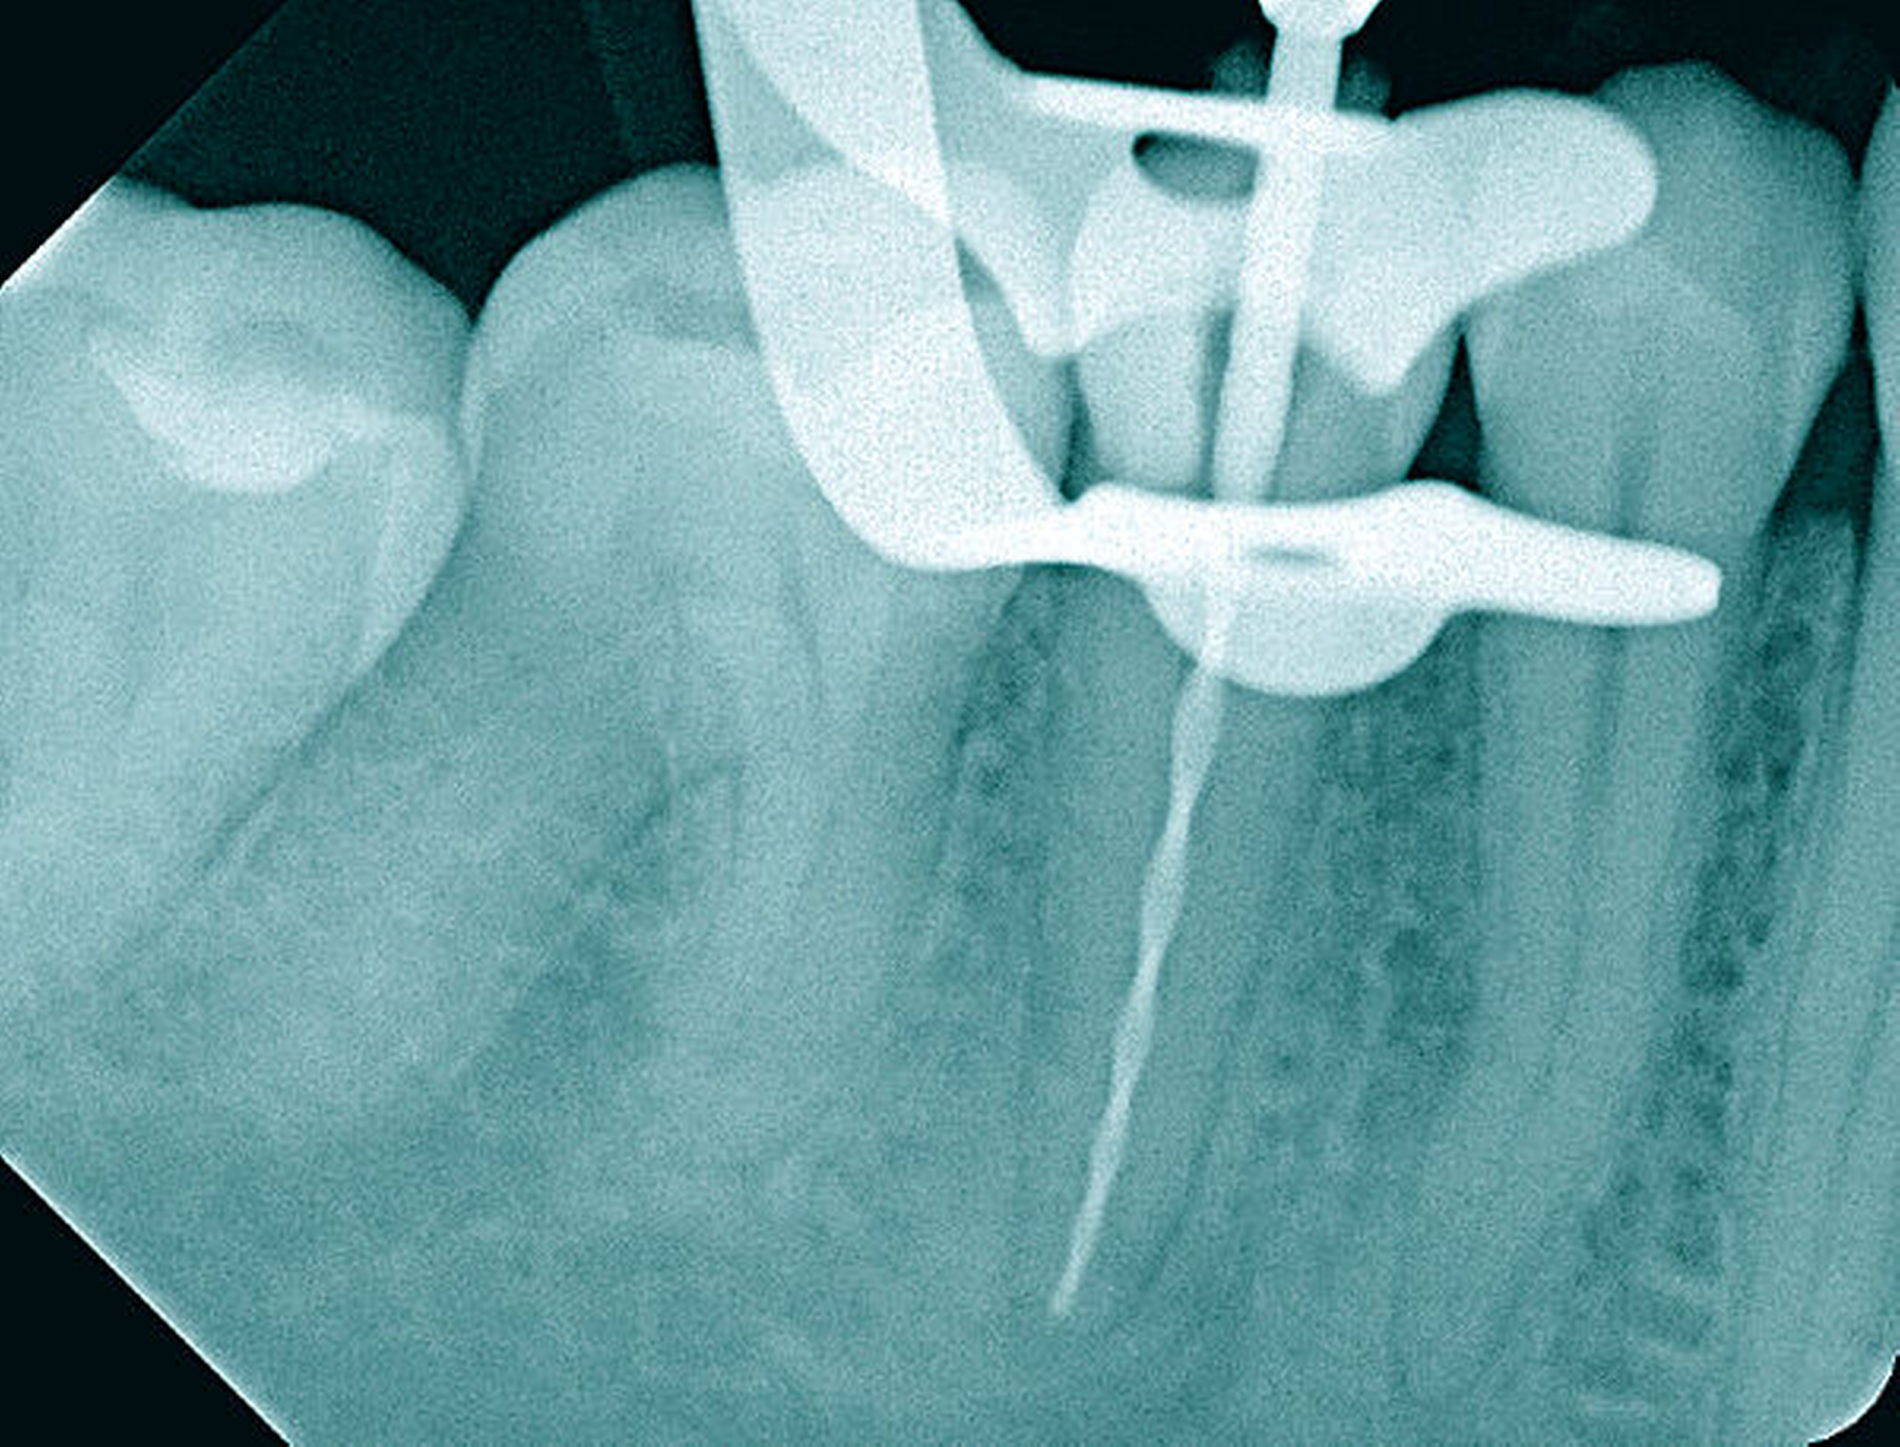

Die Therapie erfolgte unter Verwendung von Kofferdam und Lupenbrille. Die mechanische Erweiterung des Wurzelkanals und die Wurzelkanalfüllung erfolgten nach elektrometrischer und röntgenologischer Arbeitslängenbestimmung (Abbildungen 11b und 11c). Nach Abschluss der Wurzelkanalbehandlung war die Patientin beschwerdefrei.

Der Schwierigkeitsgrad entspricht dem Grad II. Sowohl in der Diagnostik als auch in der Therapie liegen erhöhte Anforderungen vor. Der Allgemeinzustand, die verringerte Compliance, die eingeschränkte Mundöffnung und das erschwerte intraorale Röntgen ließen bereits im Verlauf der Befundaufnahme eine größere Schwierigkeit erkennen. Die Wurzelspitze ist stark nach mesial gekrümmt. Der sehr kleine Krümmungsradius kann eine Instrumentenfraktur begünstigen. Die Bedingungen für einen aseptischen Zugang unter Kofferdam lagen nicht vor, so dass vorbereitend eine Kariesentfernung und eine dentinadhäsive präendodontische Restauration erforderlich wurden (Abbildungen 13a und 13b).